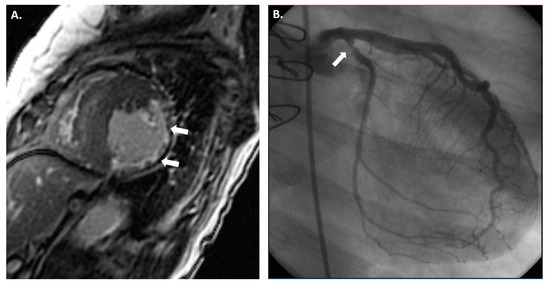

The International Society for Heart and Lung Transplantation (ISHLT) recommends ICA as the gold-standard method for the diagnosis and surveillance of CAV (Figure 1) [3]. Typically, ICA is recommended one month after HTx and then annually or biannually; however, it may be required less frequently if no apparent symptoms or signs of CAV are found three to five years after HTx [12]. Based on angiographic findings and evidence of graft dysfunction, the ISHLT criteria classify CAV into four grades, as follows: absent (CAV0), mild (CAV1), moderate (CAV2), and severe (CAV3) [2,3,13] (Table 1). Although widely available in most institutions, ICA has several considerable drawbacks. One significant limitation of ICA is its reported insensitivity to detect diffuse concentric lesions, as seen in early CAV, as it cannot visualize beyond the arterial lumen [12,14].

Figure 1.

A 53-year-old male patient who developed severe CAV two years after HTx. (A) Successful intervention of the middle left anterior descending artery (green circle) with one drug-eluting stent (preintervention stenosis was 90%). (B) Successful intervention of the middle right coronary artery (green circle) with one drug-eluting stent (preintervention stenosis was 70%).